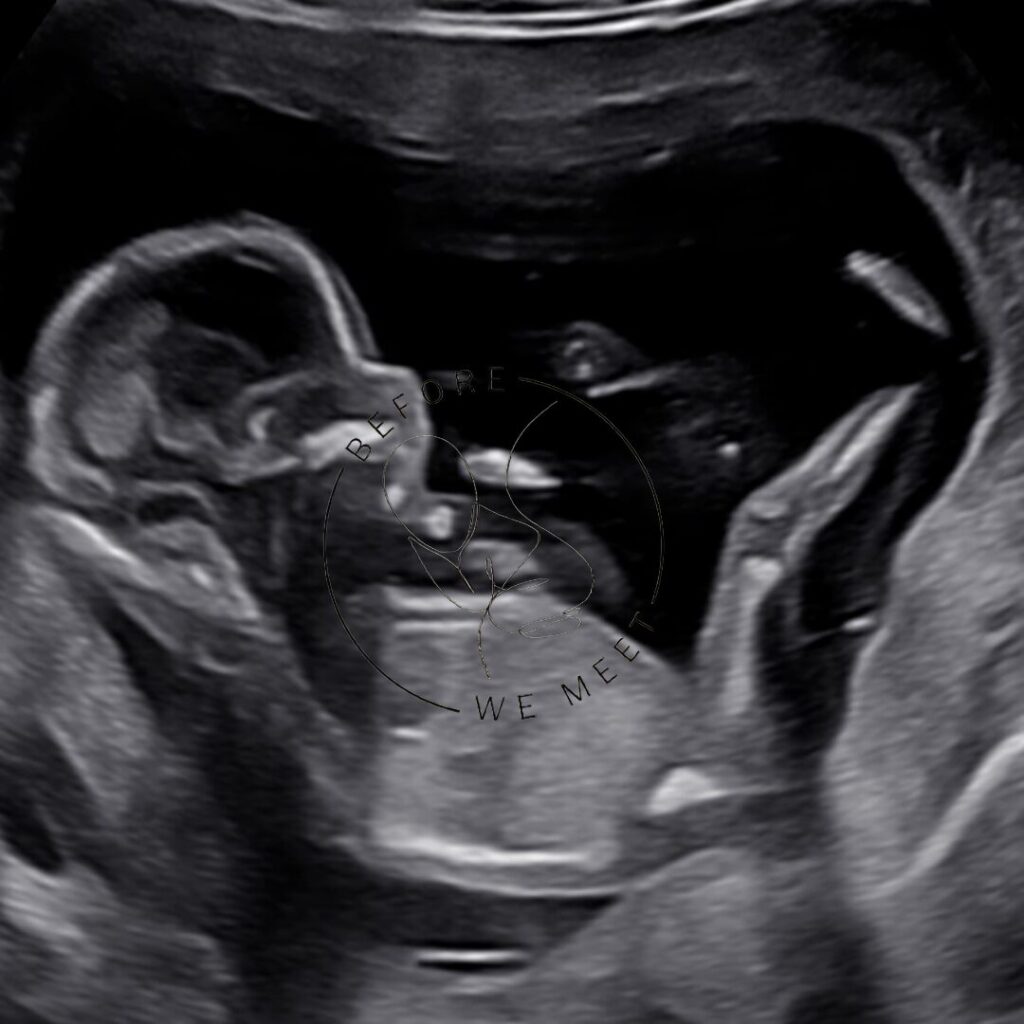

Veel ouders kiezen voor een pretecho als herinnering aan de zwangerschap of om samen met familie of vrienden extra naar de baby te kijken. Bij een 3D- of 4D-echo zien we duidelijk het gezichtje in kleur en zien we soms een lachje of een gaapje!

2D pretecho (7-40 weken)

- Inclusief: 4 zwart-wit foto afdrukken